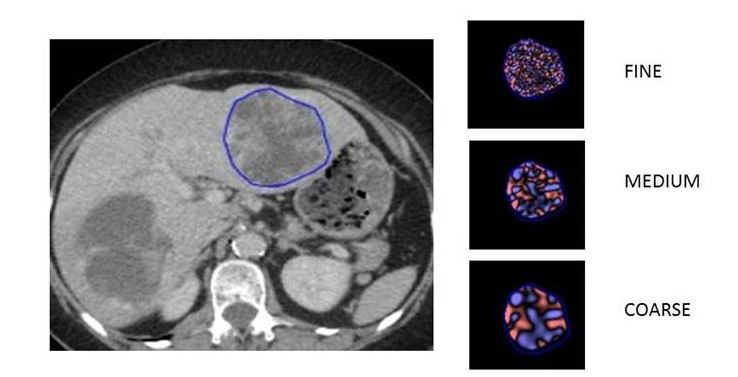

Article: Metastatic melanoma: pretreatment contrast-enhanced CT texture parameters as predictive biomarkers of survival in patients treated with pembrolizumab